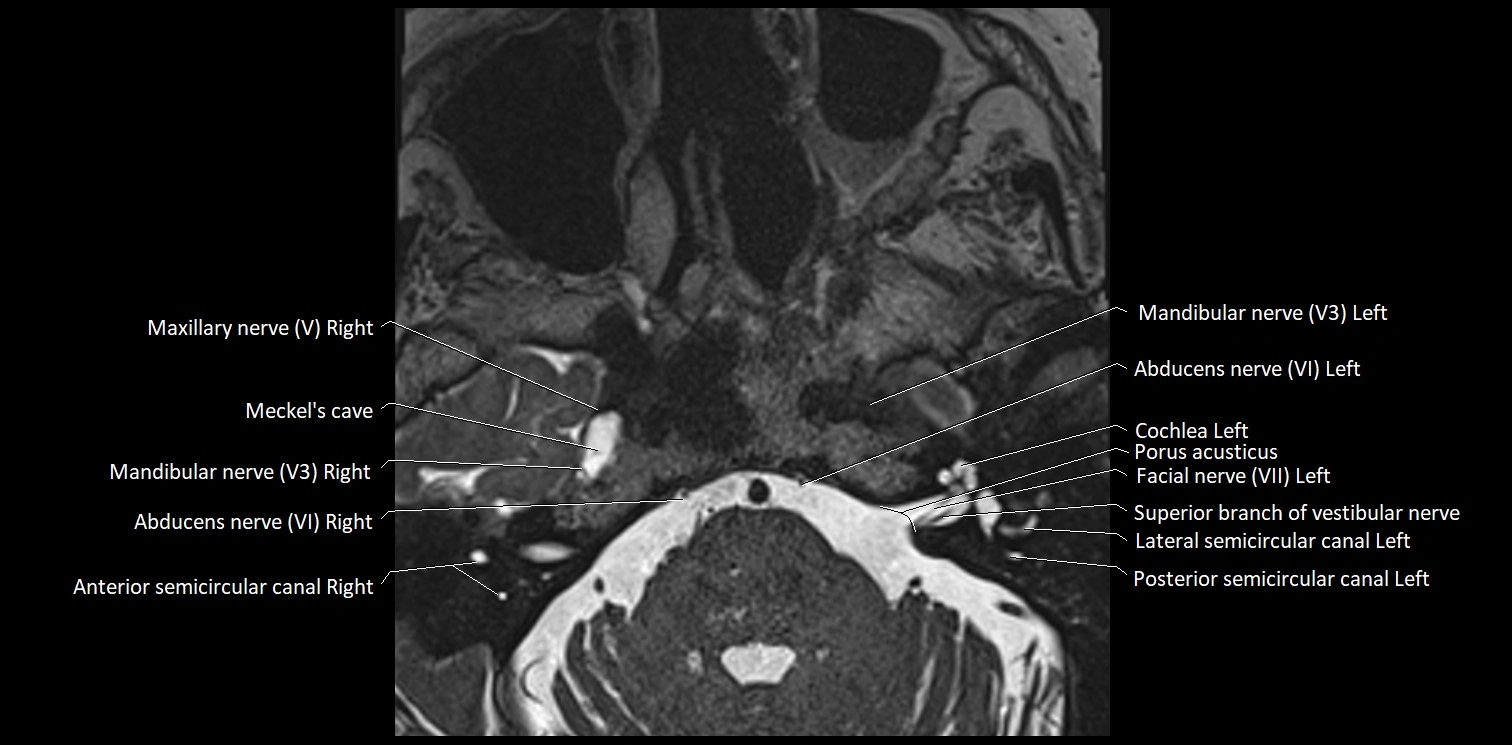

MRI Appearance

• The abducens nerve is a small, thin, linear structure

• Best visualized on high-resolution T2-weighted 3D MRI sequences (e.g., FIESTA or CISS)

• Seen as a hypointense (dark) line running from the brainstem at the pontomedullary junction, traversing the prepontine cistern, and entering Dorello’s canal under the petrosphenoidal ligament, then into the cavernous sinus, and finally the orbit

• May be challenging to visualize in standard MRI due to its small size

• Pathology may be inferred by absence, displacement, or enhancement of the nerve